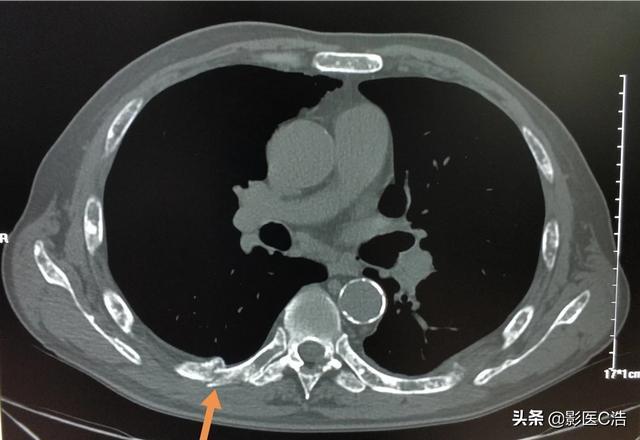

骨転移が骨、一般的には肋骨に発生した場合にも病的骨折が起こることがありますが、これは転移が骨の正常な構造を破壊するため、骨が弱くなり、外力が加わったときに骨折しやすくなるためです。骨転移の中には、骨の周囲に軟部組織の腫瘤として現れるものもありますが、体表には現れないため、発見するのは容易ではありません。病的骨折(下の矢印)